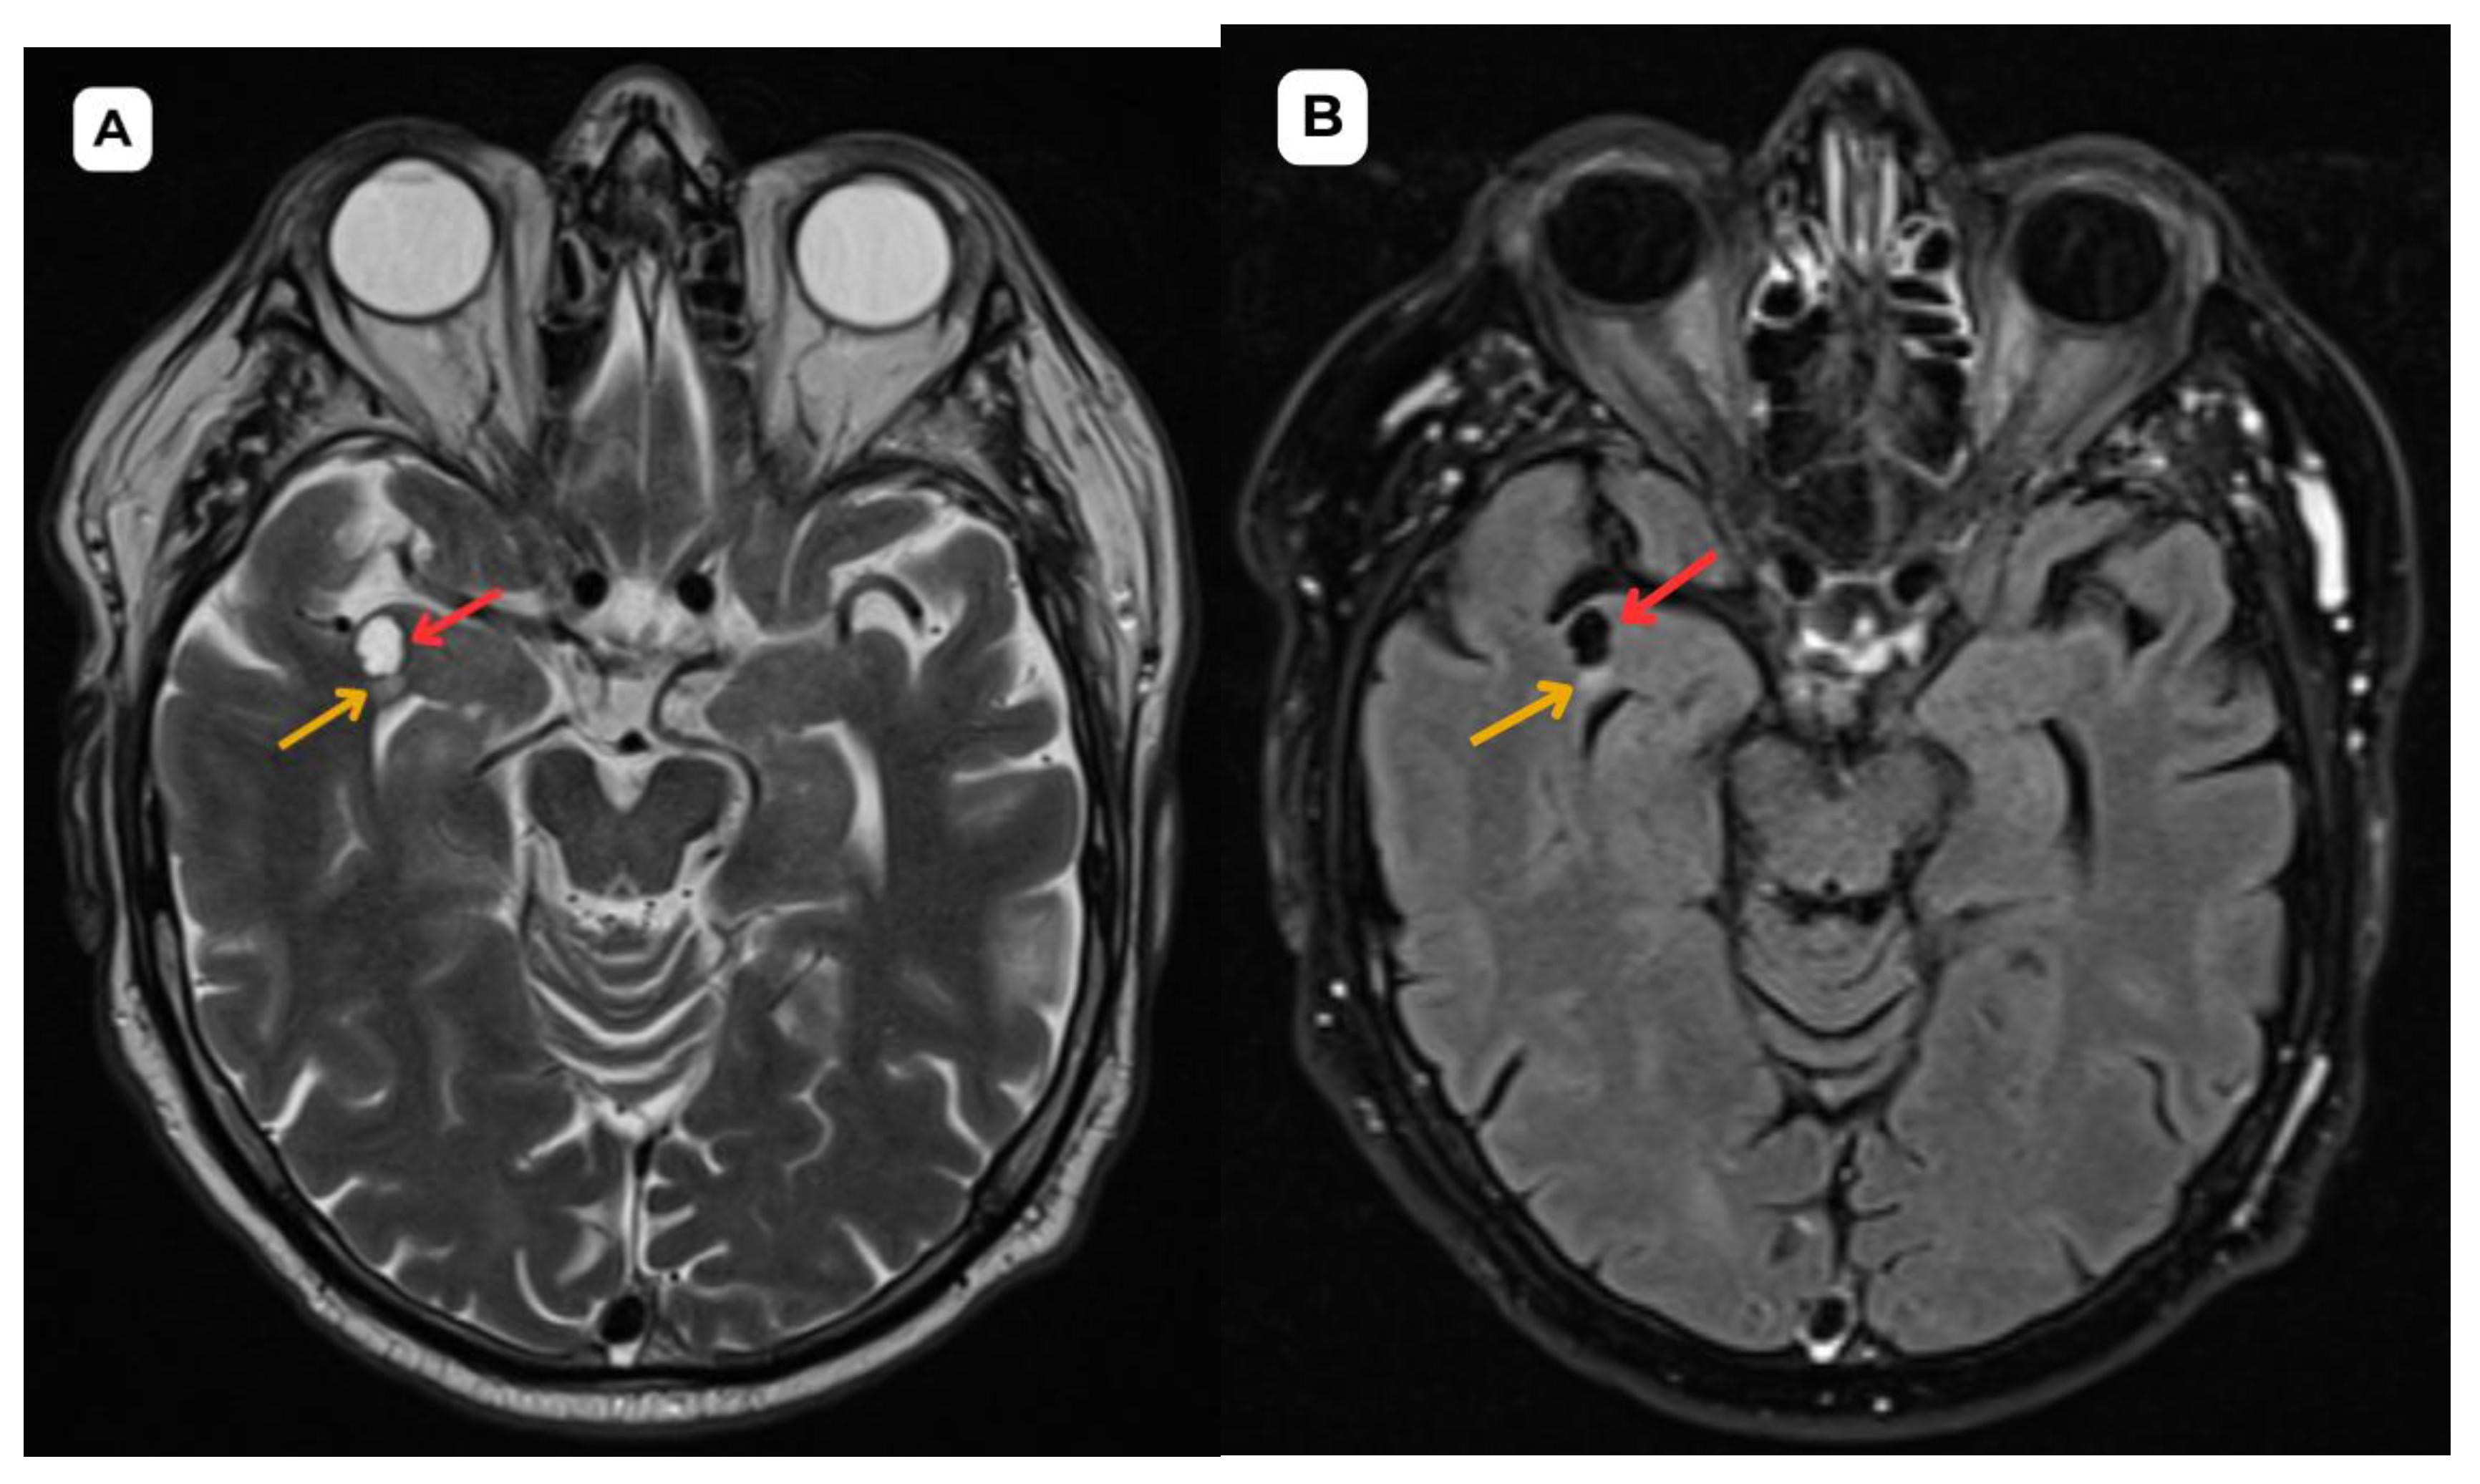

Figure 2. First patient: brain MRI of a 63-year-old male. A: SWI—susceptibility weighted imaging, axial. No evidence of blood products or hemosiderin is seen, supporting a non-hemorrhagic, benign nature of the cystic lesion. B: T1 axial post-contrast sequence shows no abnormal contrast enhancement in the cystic lesion, with no features suggestive of malignancy or disruption of the blood–brain barrier. Red arrow—opercular (type IV) perivascular space, yellow arrow—surrounding edema.

In magnetic resonance imaging, the signal intensity of the opercular perivascular spaces themselves is identical to that of cerebrospinal fluid in all sequences—hypointense on T1W1 and FLAIR, hyperintense on T2W1, and the ADC value corresponds to cerebrospinal fluid [6,7]. In both of these cases, MRI images were acquired with the Siemens “MAGNETOM Sola” 1.5T system. In both cases, cerebrospinal fluid signal is visible in all MRI sequences. In the images, these PVS are located very close to the branches of the middle cerebral artery, which come into contact with the cerebral cortex, with MRI showing regional cortical thinning in the brain [6,7].

The presence of cerebrospinal fluid intensity tracts in the images is also useful as a radiological criterion for the diagnosis of perivascular spaces [1]. All the above-mentioned features help distinguish opercular perivascular spaces from neuroglial tumors with characteristic perifocal edema.

In MRI imaging, opercular perivascular spaces can also be differentiated based on their appearance: round, oval, or tubular, well-defined cystic structures that do not contain calcifications, hemorrhagic elements, or high-protein content structures. In both cases, opercular perivascular spaces appear round (Figure 1, Figure 2, Figure 3, Figure 4, Figure 5 and Figure 6). These formations do not enhance with contrast, which also helps to distinguish them from other pathologies. In both of the cases no contrast enhancement was seen (Figure 1, Figure 2, Figure 3, Figure 4, Figure 5 and Figure 6). It is important to highlight the pathognomonic feature—visualization of the perforating central artery of the perivascular space—using TOF combined with 3D CISS sequences [8].